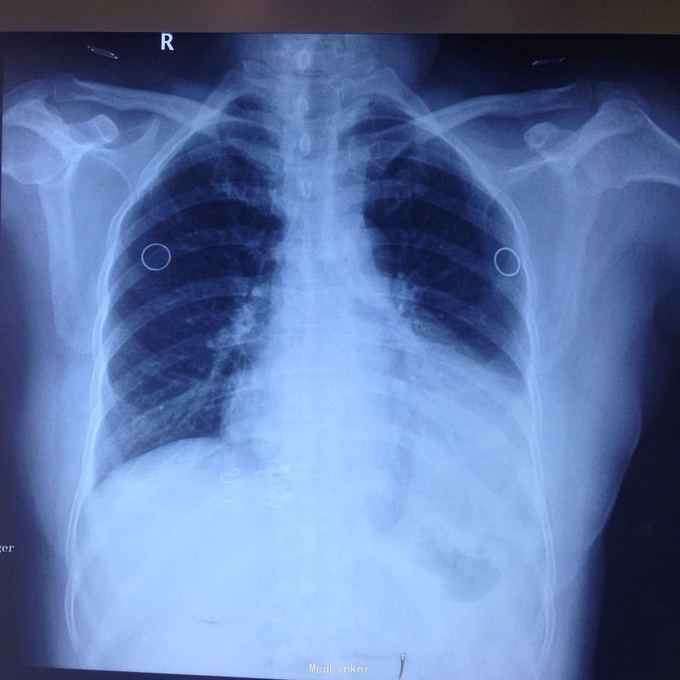

主诉:发现胸腔积液4月余。 现病史:患者4个月前因腰椎间盘突出在当地医院就诊,检查发现双侧少量胸腔积液,量不多,2个月后胸闷气短再次在当地医院复查胸部ct,提示双侧胸腔积液较前增多,左侧明显。

查体:女性患者,45岁,体温正常,一般情况可,颈软,气管居中。左下肺呼吸音稍低,右肺呼吸音清,未闻及干湿性啰音。心率80次/分,律齐,无杂音。

左侧胸腔包裹性积液? 完善胸腔b超提示左侧胸腔包裹性积液,最深处约59mm,内透声较差。予以定位后诊断性穿刺未抽出明显液体,当时考虑液体可能较粘稠或包裹分隔,遂决定予以小切口开胸探查。开胸后见胸腔积液,量约300ml,颜色较清亮,予以抽吸后在探查,见脏层及壁层胸膜无增厚及明显粘连,遂考虑不排除囊肿可能性,继续探查见胸膜顶靠近左纵隔处一囊壁,已破裂,囊壁挛缩成团,予以切除,术后病检为胸腺囊肿。

术后病检为胸腺囊肿。术后讨论:患者多次胸部ct均提示为包裹性积液,因囊肿较大,囊壁较薄,且靠近胸壁,易误诊为包裹性积液,但患者一直无发热病史,且复查ct积液位置靠胸前壁,术前应该考虑到囊肿可能,因患者经济较困难,至本院后未行增强ct,穿刺后考虑穿刺针将囊壁穿破,故开胸后未见完整囊肿,此类看似简单的病例容易由其他医院诊断误导,并且容易误诊。